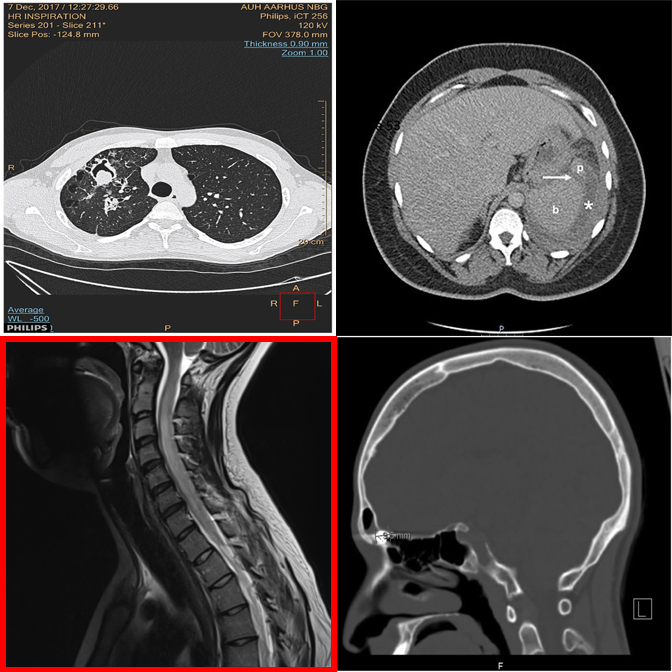

Anatomy and viewpoint mismatches. E.g., one abdomen CT among chest X-rays.

The dense 3×3 layout overwhelms systematic comparison — picks wrong column.

Falls back to default position under uncertainty in the dense grid.

3×3 grids universally expose shallow pattern matching.

Referring MCQ gives a text hint about the anomaly type, making it easier to verify.

Cross-anatomy mismatches are easier when the anomaly type is described.

Referring MCQ typically achieves higher accuracy than detection protocols.